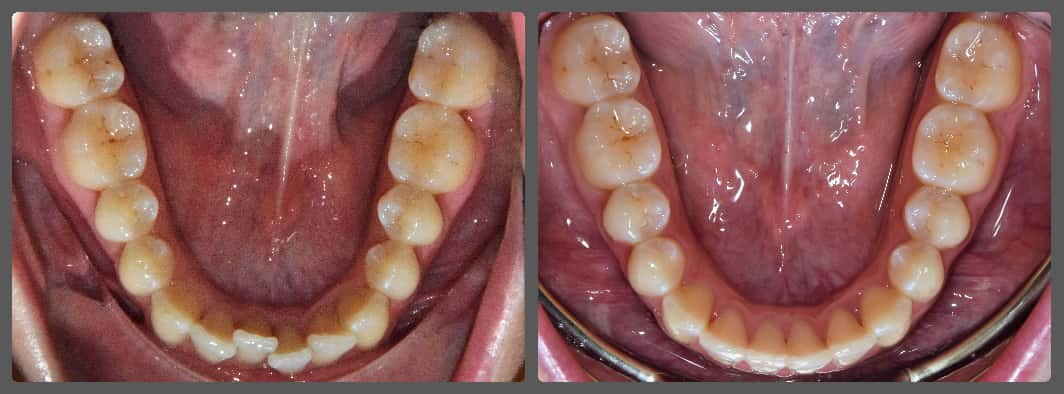

Zoli torlódott alsó fogai miatt szeretett volna fogszabályozó készüléket. Régebben 2 db felső kisőrlő fog eltávolításával már fogszabályozták, azonban az alsó fogív eltérései jelentősek voltak. A torlódás mellé közepes mértékű mélyharapás társult, valamint a bal oldali kisőrlő fogaknál non-occlusiot figyeltem meg. Ez azt jelenti, hogy esetünkben a felső első kisőrlő fog az alsó első és második kisőrlő fog közé, de azok külső felszínére harap. Ez a felső fogat kifelé, az alsókat befelé, a nyelv felé dönti és hosszútávon súlyos elváltozást okoz. Alsó-felső Pitts21 rögzített fogszabályzóval, intermaxilláris gumihúzással, harapásemelőkkel és tolórugókkal Zoli fogait nagyon gyorsan, 13 hónap alatt sikerült tökéletes pozícióba szabályoznunk, mind esztétikai, mind funkcionális szempontból (persze ehhez kellett a töretlen lelkesedése, együttműködése is). A kezelés végén az alsó fogívre fix retainert helyeztem fel az elért állapot megőrzésére. A végeredmény úgy gondolom mindent elmond!